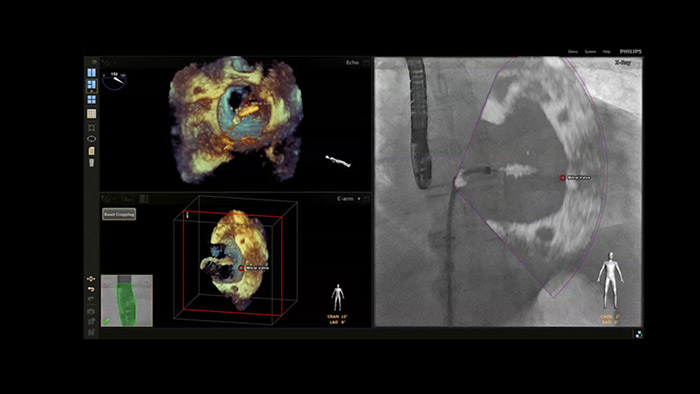

EchoNavigator mit Anatomischer Intelligenz

Um Ihr Verständnis anatomischer Strukturen und der Platzierung von Kathetern und Geräten bei einem interventionellen Herzverfahren zu verbessern, ermöglicht das Philips EPIQ CVxi eine modalitätenübergreifende Entscheidungsunterstützung.